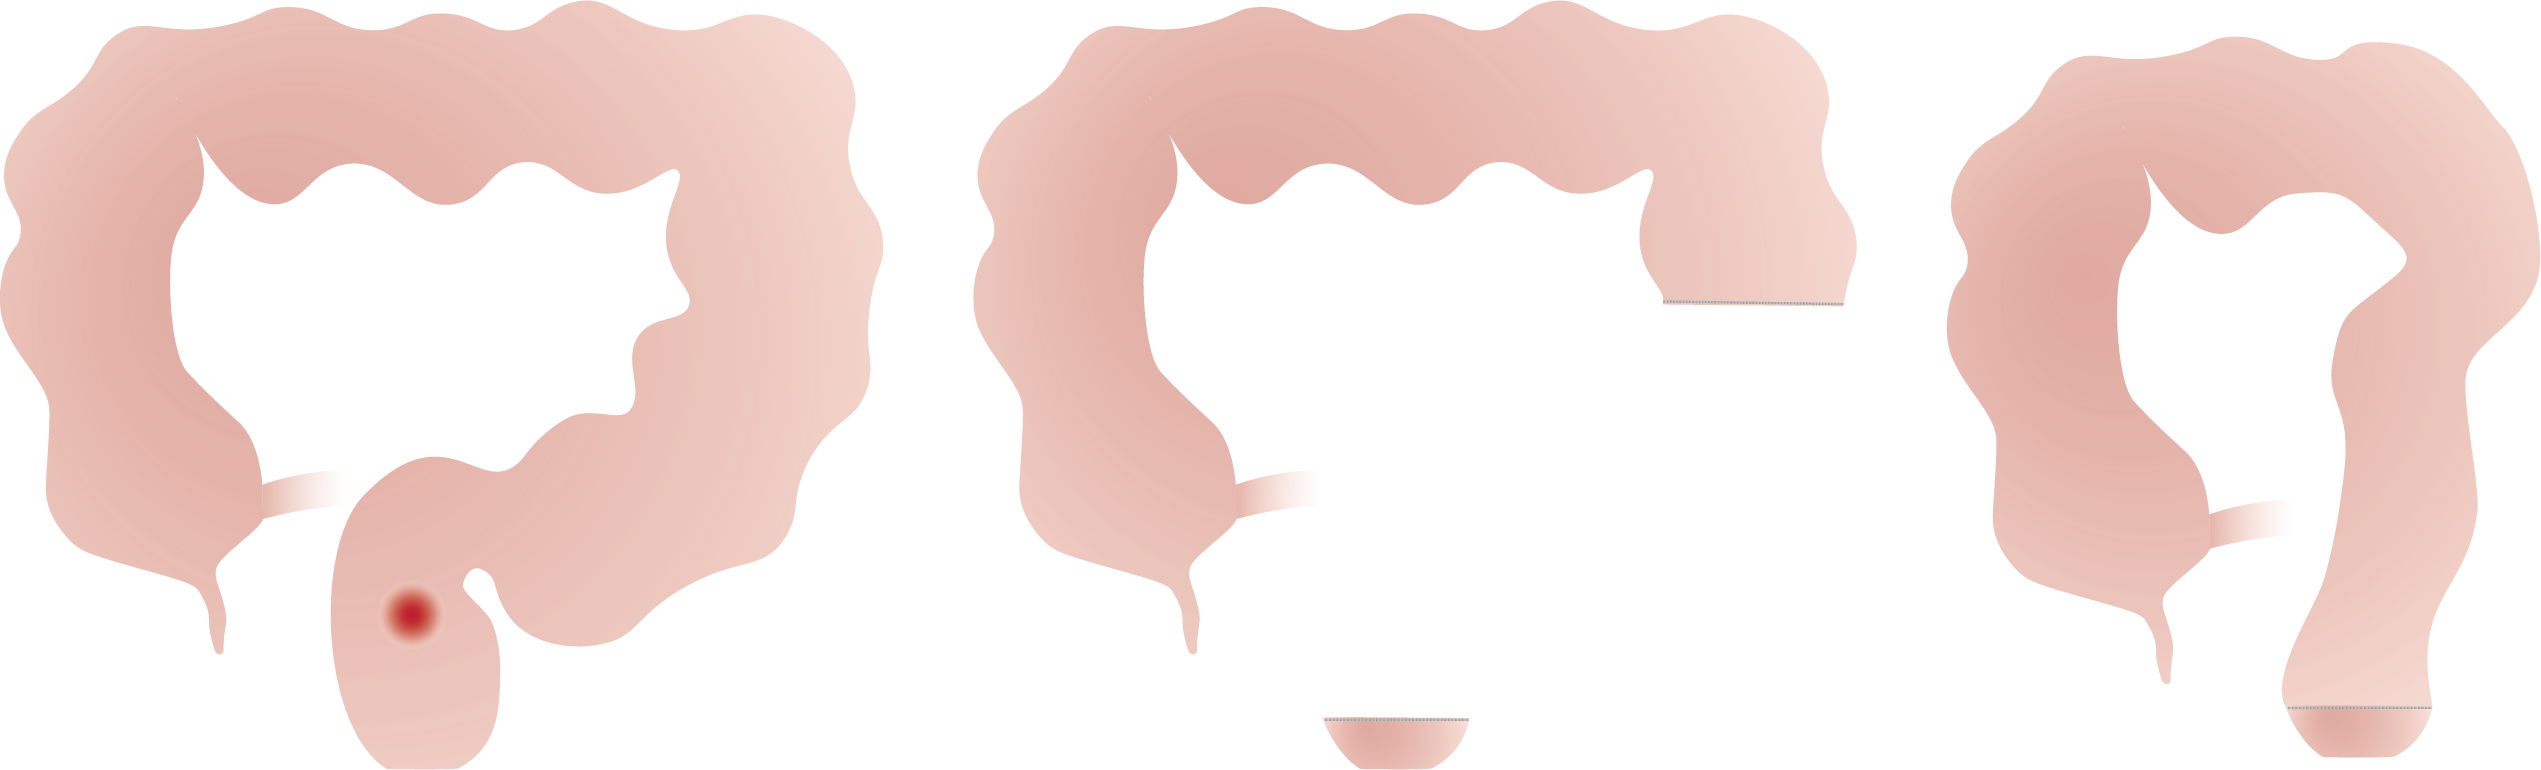

Dikkedarmkanker, ook wel colonkanker of coloncarcinoom genoemd, is een veelvoorkomende en potentieel levensbedreigende aandoening die ontstaat in de dikke darm, het laatste deel van het spijsverteringsstelsel. Deze vorm van kanker ontstaat doorgaans uit een ongecontroleerde groei van slijmvlies tot poliepen die, indien onbehandeld, verder kunnen uitgroeien tot kwaadaardige tumoren.

Bij een operatie voor darmkanker verwijdert de chirurg behalve de tumor aan beide kanten van de tumor ook een stukje gezond weefsel en een deel van het vet met lymfeklieren vlak bij de tumor. Deze lymfeklieren worden nadien onderzocht onder de microscoop. Afhankelijk van de uitslag bepaalt de arts of er een reden is om aanvullend chemotherapie te adviseren.

Afhankelijk van de locatie van de tumor moet dus een ander stukje van de dikke darm en zijn bloedvoorziening worden mee weggenomen.

Naargelang de plaats van de aandoening spreekt men van een:

• Linker hemicolectomie (colectomie = verwijderen van dikke darm, hemi = half) en sigmoidectomie (wegnemen van het voorlaatste deel van de dikke darm).

• Rechter hemicolectomie (colectomie = verwijderen van dikke darm, hemi = half).

• Rectum resectie (= verwijderen van de endeldarm zonder de anus).

• Rectumamputatie (= verwijderen van de endeldarm met de anus).

• Totale colectomie (= verwijderen van de hele dikke darm met eventueel dunne darm 'pouch').